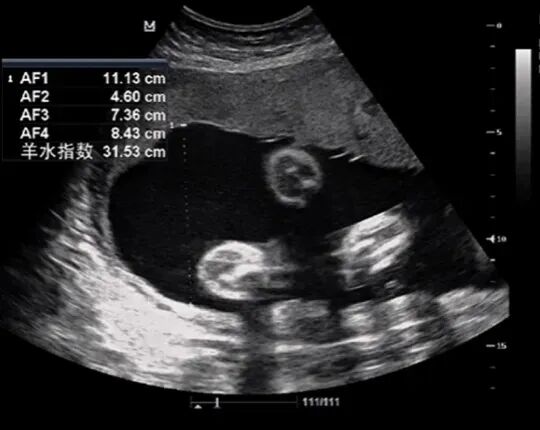

柳女士,35岁,已妊娠31周余,产检做三级产科超声发现羊水过多、胎儿心包积液。